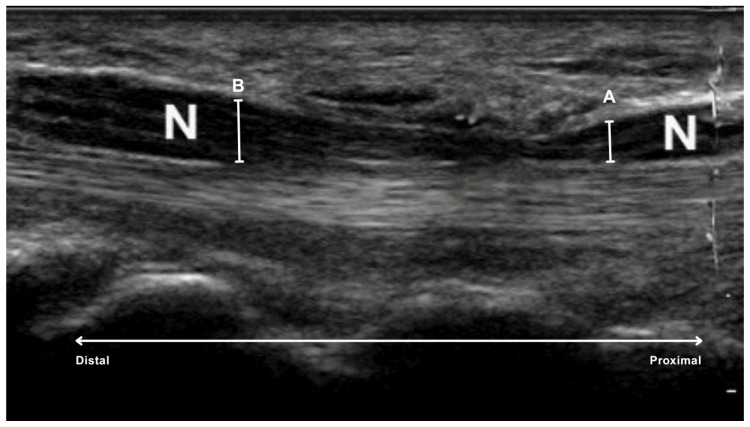

Background: Carpal tunnel syndrome is a common entrapment neuropathy of the upper limb that has a significant clinical and socioeconomic impact. Sonographic short-axis measurement of the median nerve cross-sectional area is a well-established complement to clinical examination and neurography. This study aimed to evaluate the correlation between the median nerve diameter ratio, distal motor latency, and sensory nerve conduction velocity. Methods: A total of 74 patients (94 hands and 93 evaluations) with carpal tunnel syndrome were examined. Ultrasound was performed using a Siemens Acuson X300 with a 10 MHz linear probe. Median nerve diameters proximal and within the carpal tunnel were measured in a longitudinal scan. The carpal tunnel ratio (proximal diameter/intratunnel diameter) was then calculated and correlated with distal motor latency. Results: No significant correlation was found between distal motor latency and the carpal tunnel ratio (r = 0.018, p = 0.8655). However, a weak, non-significant positive correlation was observed between sensory nerve conduction velocity and carpal tunnel ratio (r = 0.238, p = 0.326). Conclusions: Ultrasound cannot replace electrodiagnostic testing. In this cohort, no statistically significant association was observed between the carpal tunnel ratio and distal motor latency. While our findings do not support the use of this ultrasound parameter as a standalone diagnostic measure, sonographic assessment of the median nerve may still provide complementary information in selected clinical contexts.